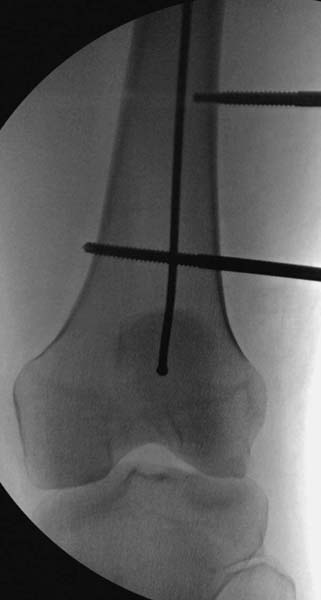

Остеосинтез бедра не стали делать из-за множественных переломов ребер с ушибом грудной клетки и поэтом у закончили фиксацию бедра наружным фиксатором.

Около 11.00 вечера больная переведена в реанимацию, без сознания, но стабильная.. На третьий день провели стабилизацию перелома бедра антеградным остеосинтезом.